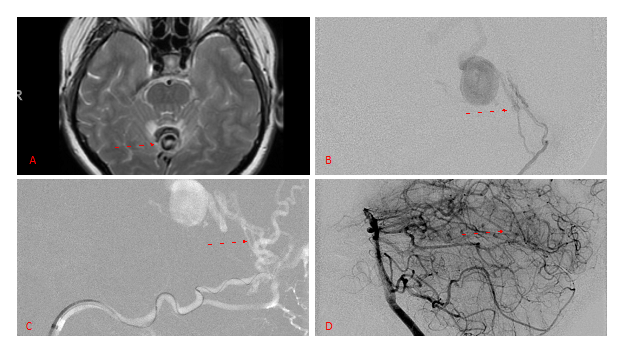

No severe neurologic deficits were observed initially. Her cerebral angiogram revealed a high flow Dural arterial venous fistulous malformation of the tentorium supplied by the bilateral external carotid and left vertebral arteries into a large venous varix within the fourth ventricle at the site of the hemorrhage. Deep venous drainage is observed into the Galenic and Straight Sinus of the posterior fossa (Figure 2).

Figure 2. [A] Ruptured Varix/Aneurysm of the Deep Venous Posterior Fossa drainage and AV shunting (arrows) [B] Posterior Meningeal Artery Fistula [C] Right Middle Meningeal Artery Fistula [D] Post embolization Left Vertebral Angiogram demonstrates resolution of the high flow and pressure A-V Shunting following successful embolization with liquid embolic (NBCA).